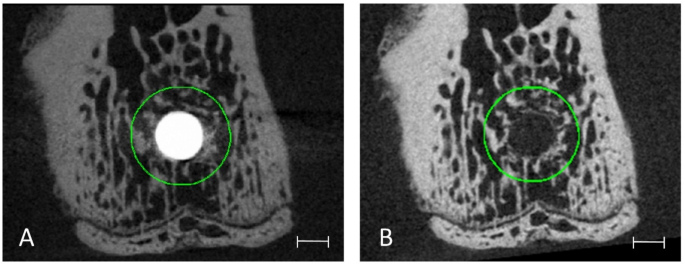

Peri-implant grey value comparison

To analyse grey value intensities in direct vicinity to the implants and to assess agreement in different regions later on, twelve standardized cylindric VOIs were determined for each T0 scan and distributed within a corridor of up to 40 voxels (405.6 μm) from the implant. The VOIs had a wall thickness of 2 voxels for the 3 cylinders closest to the implant, of 3 voxels for the next 2 cylinders, and of 4 voxels for the remaining 7 cylinders. To create these standardized VOIs, the implants were first segmented from the images using a high threshold value. Following, the implants were progressively dilated by 2 voxels after which the implant geometry of the previous dilation step was subtracted, thus leaving thin-walled cylindrical masks that were used for identification of the VOIs. As all T1 scans had been registered and transformed at an earlier step, the VOIs created for T0 scans could be applied to the respective T1 scan (Fig. 6).

Representative 2D transverse slices of one peri-implant VOI at distance of 39–40 voxels for the T0 scans (A) and its respective T1 scan (B). Note that the actual VOI is a (hollow) cylindrical region, but as it exhibits only 2 voxels of thickness it appears to be a circle. Scale bar equal to 0.5 mm.